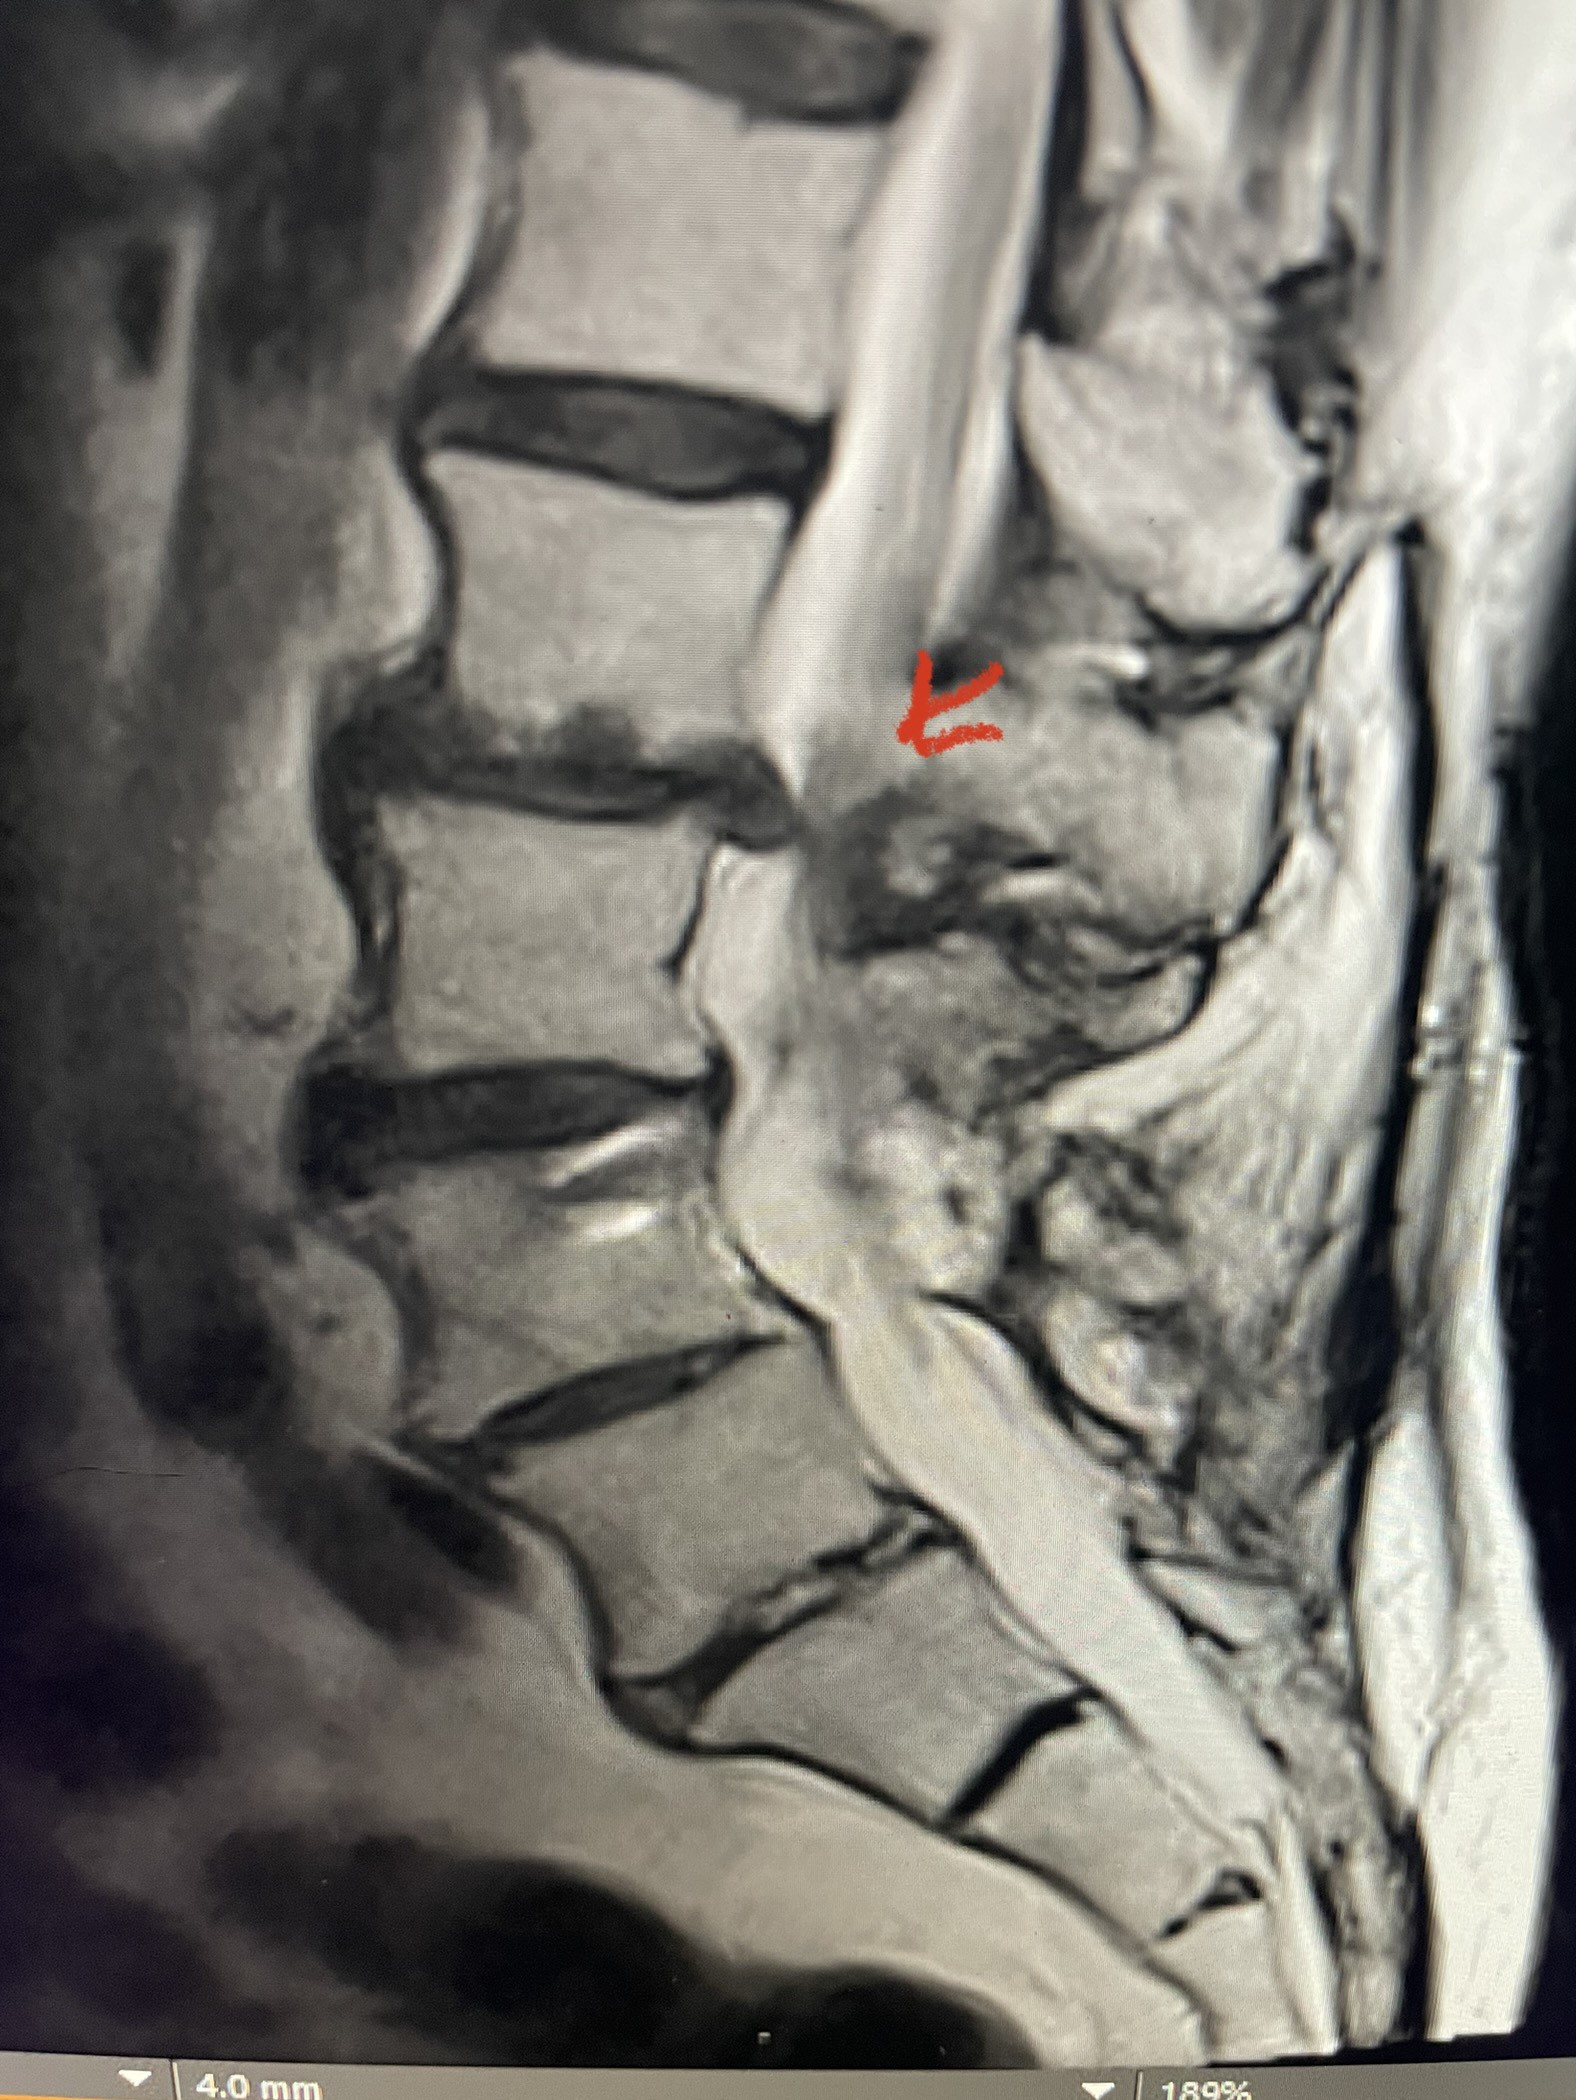

This 54-year-old morbidly obese female presents with progressive back and leg pain and quadriceps weakness. She had no diabetes. She failed all means of conservative management including physical therapy and epidural injections. On imaging she had severe stenosis at L3-4 with a disc protrusion and a slight grade 1 spondylolisthesis at L3-4 (Fig 1). We performed dynamic lumbar x-rays which demonstrated instability at L3-4 and L4-5 (Fig 2). The patient wished to have surgery. We performed an L2-4 decompressive laminectomy and L3-5 in situ fusion because of her instability. Post operatively the patient had relief of leg pain, although the patient was slow to mobilize.

Figs. 1a: Sagittal lumbar T2-weighted MRI demonstrating severe lumbar stenosis with a slight grade 1 at L3-4 and a disc protrusion (red arrow )

Fig 1b: Axial lumbar T2-weighted MRI demonstrating severe lumbar stenosis (red dot)